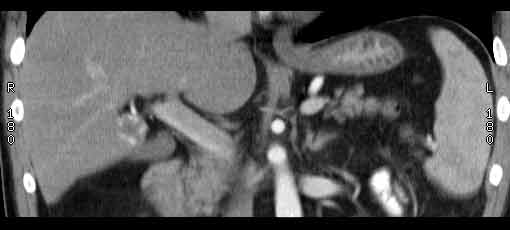

Сонограммы, КТ- артериальная, портальная и отсроченная паренхиматозная фазы

Сделали КТ (весьма похвальная тактика); по КТ: в артериальную фазу: периферическое усиление в виде сливающихся островков контраста, с центрипетальной направленностью. Венозная и отсроченная фаза-хорошее накопление контраста; образование практически изоденсно по отношению к паренхиме печени. Классика гемангиомы. Вуаля-диагноз на "тарелочке".